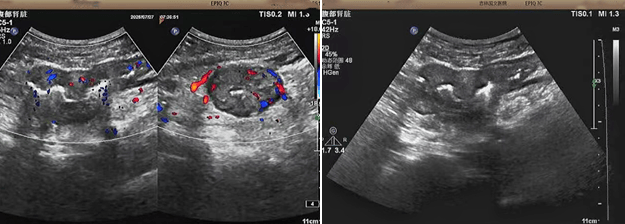

超声检查的结果进一步揭示了病情的细节:下腹部偏左肠壁显著增厚,原本清晰的层次结构遭到破坏,周围脂肪间隙变得模糊,网膜回声也出现增强的现象;同时,肠腔狭窄的情况也得到了确认。经过完善的检查,最终将病变精准定位在乙状结肠 - 直肠交界区,并且对病变范围及周围浸润情况做出了评估,这些关键信息为后续的诊疗工作提供了重要依据,让医生们能更有针对性地制定治疗方案。

我院超声检查在此次诊疗过程中展现出了显著的技术亮点。一方面,它能做到 “明察秋毫”,通过高频探头可以清晰地显示肠壁各层结构的变化,为临床判断病变性质提供了客观、准确的依据,让医生能更清晰地了解肠道内部的病变状态,另一方面,它实现了 “精准评估”,不仅准确找到了病变的位置,还能全面评估病变对周围组织的影响,这对于协助医生制定科学合理的治疗方案起到了至关重要的作用,有助于提高治疗的有效性和安全性。